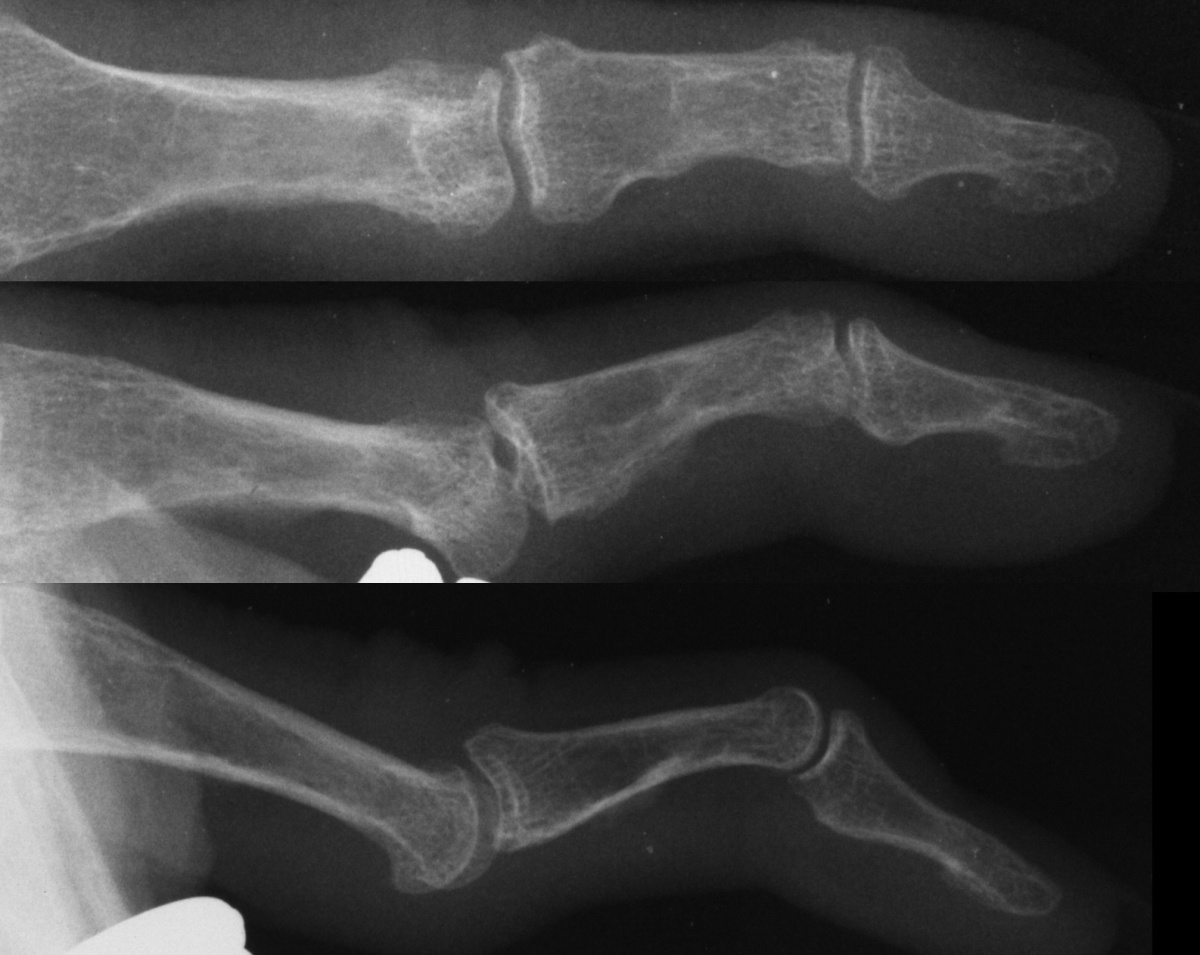

| Five years postop, with painless snapping swan neck deformity, clinically and radiographically: |

| Range of motion five years postop: soft snapping, loss of full PIP flexion, rubbery DIP flexion contracture. Palmar prominence of the proximal phalanx head due to hyperextension may be confused with a Dupuytren's nodule: |